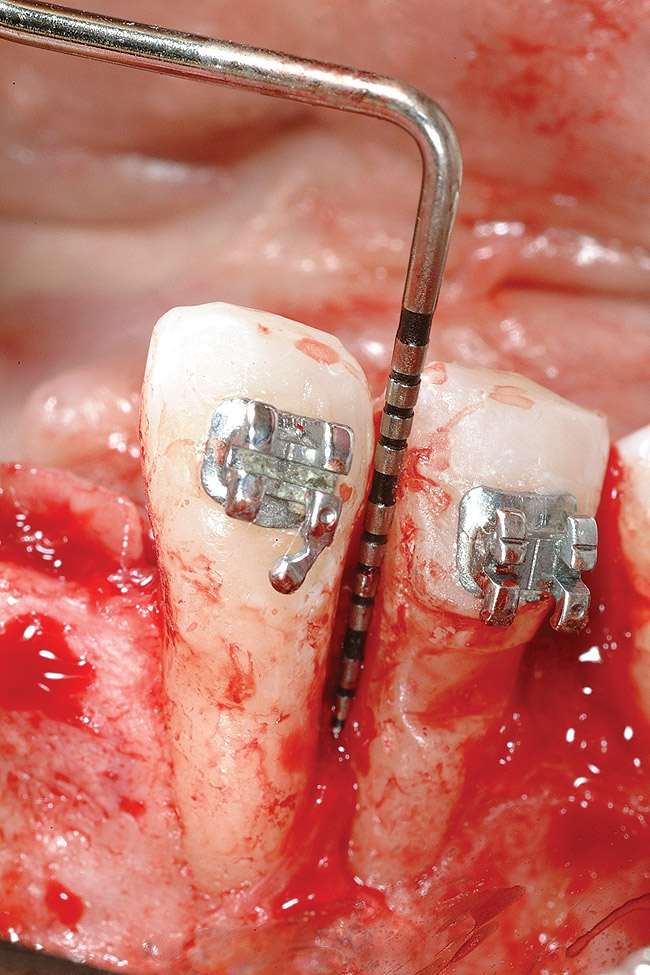

Figure 14  Interproximal bone present at teeth Nos. 21 and 22, postorthodontics.

Figure 14

Following the first goal of orthodontia—moving tooth No. 22 to a proper functional and anatomical position—a periodontal reevaluation was performed, demonstrating an improvement in short- and long-term tooth prognosis. At this time, the decision was made to abort continual extrusion of teeth Nos. 21 and 22, although some attachment level discrepancy remained between Nos. 21 and 22 (Figure 14). Implant diagnostics ensued and included mounted study models and a diagnostic wax-up. A scanning appliance was created to demonstrate the desired prosthetic outcome requirements, and the patient was referred for computed tomography (CT) scans. CT scan assessment demonstrated successful orthodontically directed GBR to allow implant placement (Figure 15 through Figure 16). Only minor GBR therapy would be needed and could be accomplished simultaneously with implant installation. Guided implant placement occurred, using an open flap approach (Figure 17). During surgery, root dehiscences were noted on teeth Nos. 21, 22, 24, and 25, as well as the anticipated dehiscence following implant placement at No. 23 (Figure 18). A positioning reference (index) was secured after implant placement to facilitate a provisional prosthesis at stage II surgery. Cortical perforations then were placed adjacent to the implant to encourage angiogenesis (Figure 18), and mineralized freeze-dried bone allograft enhanced with platelet-derived growth factor was placed over the dehiscences for purposes of guided tissue regeneration and GPR (Figure 19). A highly resorbable collagen membrane was placed to stabilize the allograft. The flap was coronally repositioned, and primary-intention wound healing was achieved (Figure 20 and Figure 21). Following 4 months of stage I surgery, implant uncovery and immediate provisionalization was performed in conjunction with connective tissue grafting. Final orthodontic tooth movement then ensued, using the implant as anchorage to optimize end-tooth movements, interroot separation, and the cuspid-protected occlusal scheme. A final impression then was secured, and a zirconia abutment (Figure 22) with an all-ceramic restoration was fabricated for the prosthetic phase completion of No. 23 (Figure 23] through Figure 25).